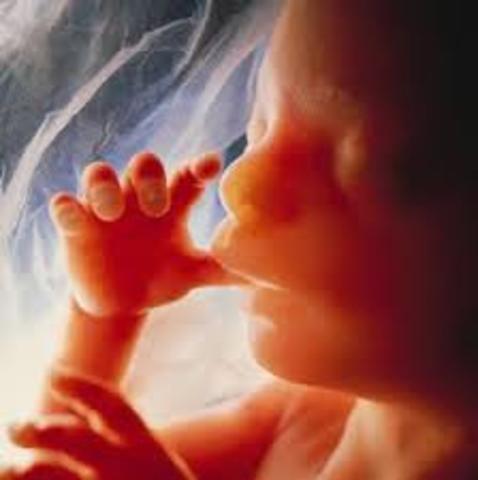

• Comienza la succión y presión del pulgar.

Comienza la succión y presión del pulgar.

No es especifico de esta fecha, sin embargo es uno de los rasgos externos mas importantes en esta semana.